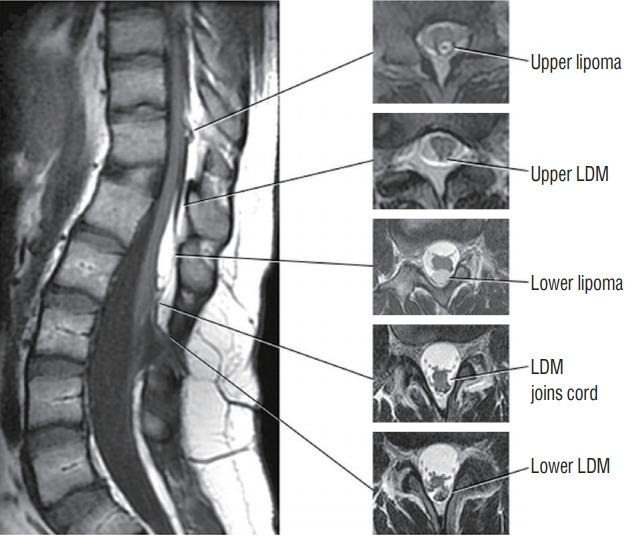

Spinal dysraphic lesions due to focal nondisjunction in primary neurulation are commonly encountered in paediatric neurosurgery, but the "fog-of-war" on these conditions was only gradually dispersed in the past 10 years by the works of the groups led by the senior author and Prof. Kyu-Chang Wang. It is now clear that limited dorsal myeloschisis and congenital spinal dermal sinus tract are conditions at the two ends of a spectrum; and mixed lesions of them with various configurations exist. This review article summarizes the current understanding of these conditions' embryogenetic mechanisms, pathological anatomy and clinical manifestations, and their management strategy and surgical techniques.

由于原发性神经管形成过程中的局灶性不分离导致的脊柱裂病变在小儿神经外科中很常见,但在过去10年中,由资深作者和王宇辰教授领导的团队的工作才逐渐驱散了这些病症上的“战争迷雾”。现在已经明确,有限性背侧脊髓裂和先天性脊柱皮样窦道是同一谱系两端的病症;并且存在各种形态的它们的混合病变。这篇综述文章总结了目前对这些病症的胚胎发生机制、病理解剖和临床表现,以及它们的治疗策略和手术技术的认识。